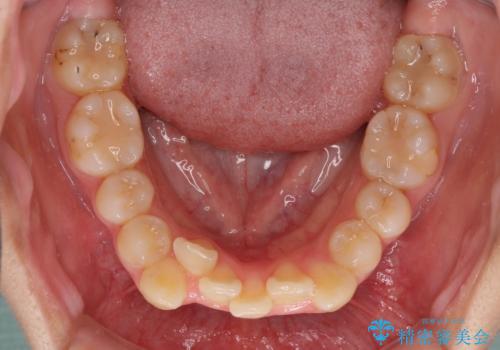

- 上下の八重歯と前歯のデコボコを気にして来院された患者様です。

右上の八重歯が特に著しく、上顎正中が右側にシフトしていました。

デコボコが強いため小臼歯4本を抜歯し、上顎正中を左側に移動させるために補助装置を使用して、ワイヤー装置にて矯正治療を行うこととしました。